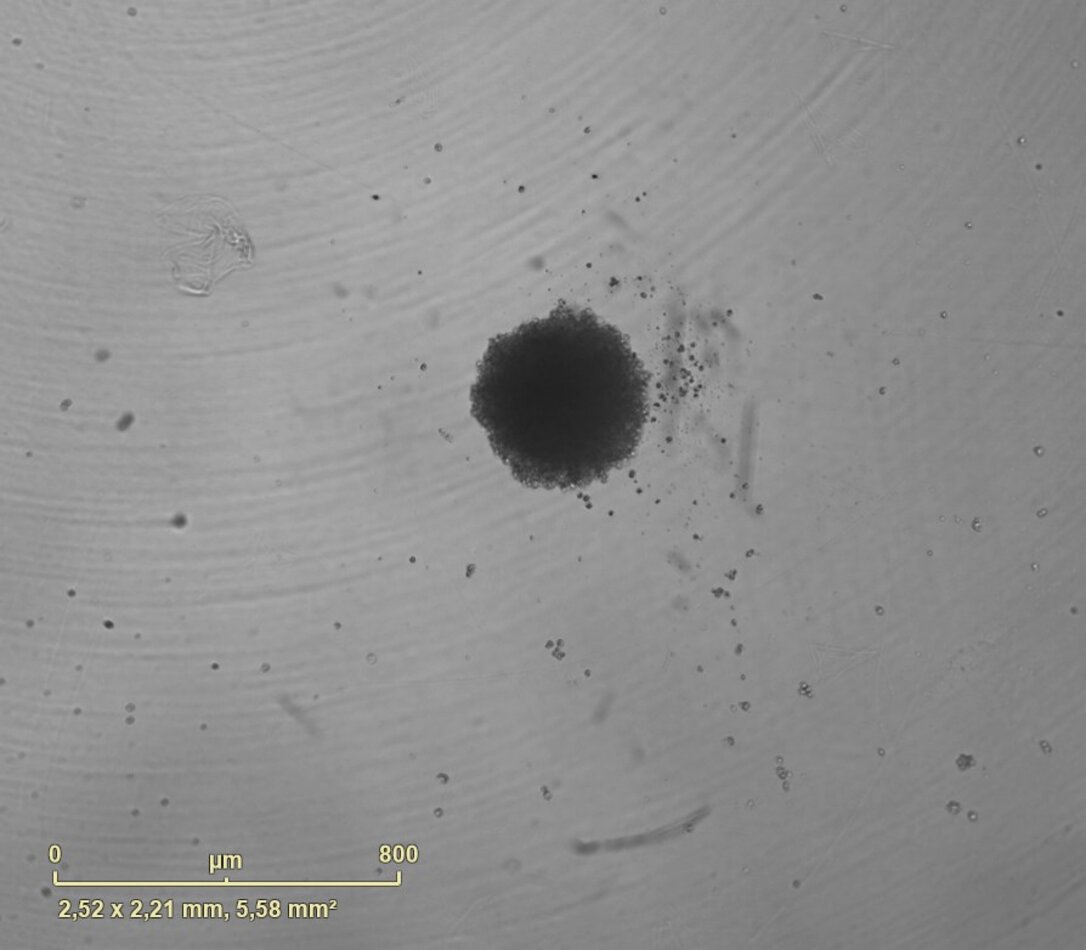

PCBIS propose un essai miniaturisé en microplaque sur sphéroïde de cellules de tumeur glioneuronale maligne pour l’évaluation de l’effet cytotoxique de composés. Celui-ci peut être quantifié soit par le suivi de la viabilité des sphéroïdes, soit par le suivi de la croissance des sphéroïdes.